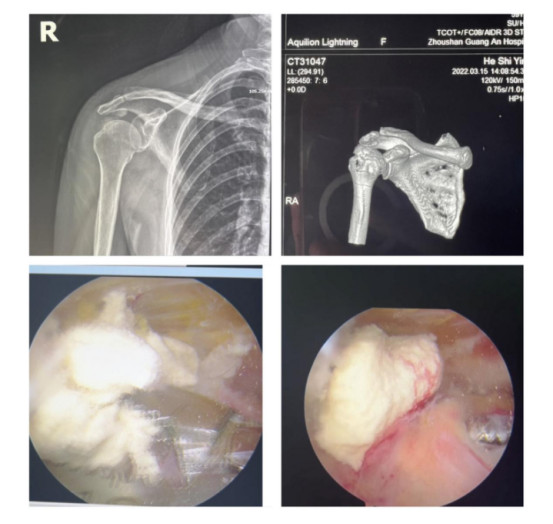

賀大媽慕名來廣安醫(yī)院找羅軍主任就診,面對羅醫(yī)生,賀大媽哭訴:“羅醫(yī)生,我真想剁下自己的這只胳膊。”羅軍主任根據(jù)患者的癥狀拍片,診斷為岡上肌鈣化性肌腱炎,隨后,羅醫(yī)生為李大媽進(jìn)行了肩關(guān)節(jié)鏡微創(chuàng)手術(shù),竟從她的右肩“擠”出“牙膏”。

鈣化性肌腱炎是一種自限性疾病,就是疾病發(fā)生發(fā)展到一定程度后,經(jīng)長期機(jī)體調(diào)節(jié)能夠控制病情發(fā)展并逐漸恢復(fù)痊愈。它分為四個(gè)階段:鈣化前期、鈣化形成期、鈣化吸收期、鈣化后期,往往在“鈣鹽斑塊”吸收時(shí),疼痛最劇烈,賀大媽就正處于“吸收期”。